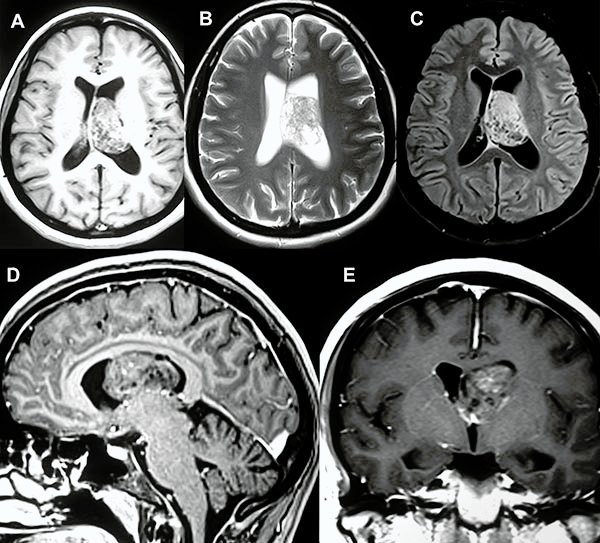

En el estudio de resonancia magnética del encéfalo se observó lesión redondeada, intraventricular a nivel de ventrículo lateral izquierdo, de bordes netos, de aproximadamente 40x30x30 mm, de señal heterogénea, predominantemente isointensa respecto a sustancia gris en T1 con presencia de focos de baja señal en su interior. En T2 se observa lesión predominantemente hiperintensa, múltiples imágenes de aspecto quístico en su interior (aspecto de burbujas) que en el FLAIR dichas imágenes quísticas son atenuadas. Tras la administración de contraste endovenoso se observa moderada y heterogénea captación del mismo (fig. 1).

Figura 1: A, B y C) Cortes axiales en las secuencias ponderadas en T1, T2 y FLAIR respectivamente. D) Corte sagital de secuencia ponderada en T1 con contraste. E) Corte coronal de secuencia ponderada en T1 con contraste.